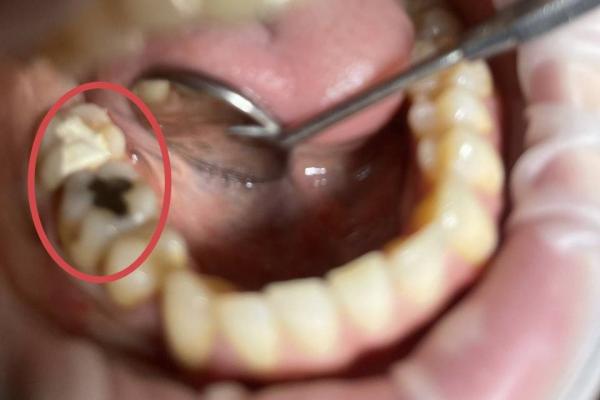

Профессиональная гигиена с использованием ультразвука включает в себя: - удаление твердых зубных отложений с помощью ультразвукового скейлера - полировка зубов профессиональной щеткой и пастой "Kerr super polish" - покрытие зубов фторосодержащим препаратом - метод рекомендован для удаления зубного камня |